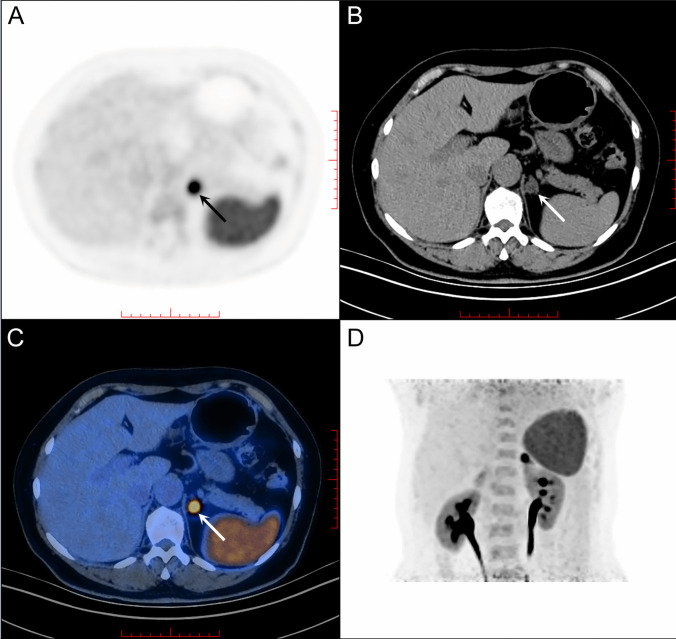

Purpose: To investigate the diagnostic efficacy of 68Ga-pentixafor positron emission tomography/computed tomography (PET/CT) in primary aldosteronism (PA) subtyping and lateralization of aldosterone secretion in PA patients.

Procedures: 37 patients who were diagnosed with PA, were prospectively enrolled in the study, and underwent adrenal vein sampling (AVS) after 68Ga-pentixafor PET/CT was conducted. Lateralization index (LI), defined as aldosterone/cortisol ratio in the dominant side to the contralateral adrenal vein when bilateral adrenal vein catheterization succeeded, and the aldosterone/cortisol ratio in the left adrenal vein to IVC (LAV/IVC) when the catheterization of right adrenal vein failed, were applied to determine lateralization side. Statistical analysis was performed using SPSS 21.0.

Results: The female proportion of all patients with PA was 32.4% (12/37), and the mean age was 51.3 ± 10.9 years. Patients with bilateral adrenal mass accounted for 54.1% (20/37), and 10 of them (27.0%) had adrenal hyperplasia or adrenal nodules ≤ 1.0 cm. In all 37 patients, the sensitivity, specificity and accuracy of 68Ga-pentixafor PET/CT in distinguishing lateralization by visualization were 89.3%, 77.8% and 86.5%, respectively. The area under the ROC curve for detecting positive lateralization based on the value of 68Ga-pentixafor SUVmax was 0.750 (95%CI 0.578-0.922, p = 0.026). The optimum SUVmax cut-off value was 6.86, with the sensitivity of 78.6%, specificity of 66.7%, and accuracy of 78.4%. Defining SUV ratio as SUVmax/SUV of contralateral adrenal gland, the area under the ROC curve for identifying lateralization based on the SUV ratio was 0.710 (95%CI 0.500-0.921, p = 0.061). The optimum SUV ratio cut-off was 2.40, with the sensitivity of 60.7%, specificity of 88.9%, and accuracy of 67.6%. The consistency of 68Ga-pentixafor PET/CT with AVS was of no significant difference between patients with bilateral adrenal lesions (80.0%, 16/20) and unilateral lesion (94.1%, 16/17; p = 0.737), and no significance was revealed in the consistency between patients with adrenal hyperplasia or adrenal lesion of diameter ≤ 1 cm (81.8%, 9/11) and those with adrenal lesions > 1 cm (88.5%, 23/26; p = 0.884).

Conclusions: 68Ga-pentixafor PET/CT showed at least 80% consistency for the lateralization in patients with PA compared with AVS, even in those presented with bilateral adrenal hyperplasia. Visual analysis exhibited better diagnostic efficacy compared with SUVmax or SUVmax/SUV of the contralateral adrenal gland.( ChiCTR2300073049. Registered 30 June 2023. Retrospectively registered).